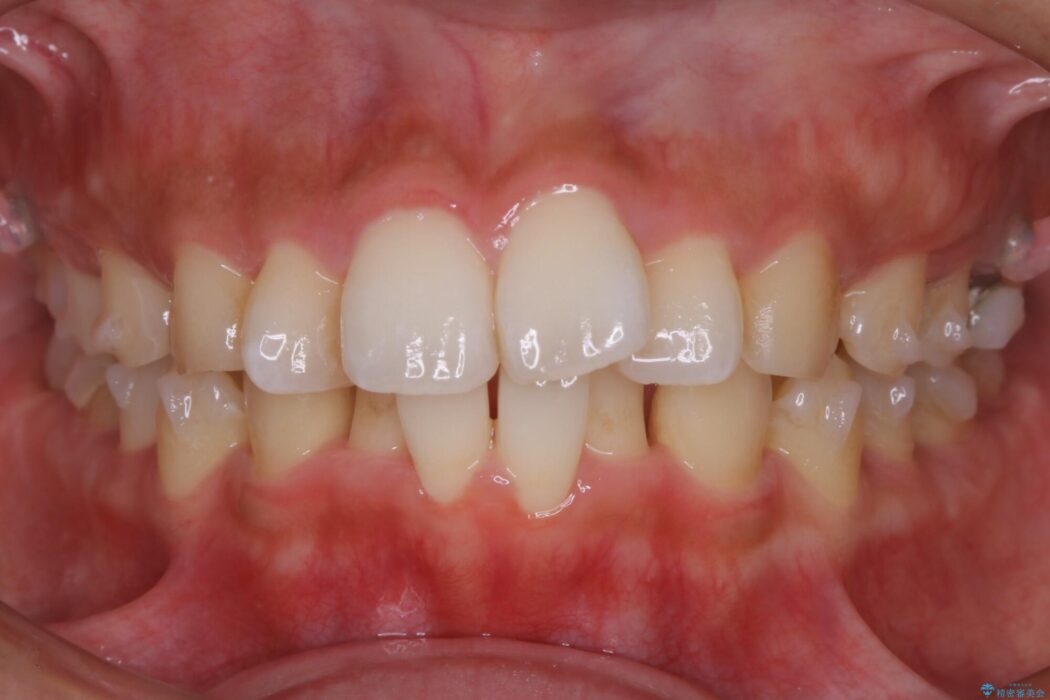

口元が後方に下がったことにより横から見たEラインが改善し、口元の印象が変わったと患者様にとても喜んでいただけました。

口ゴボに加えて歯列のガタガタを改善したいと来院されました。